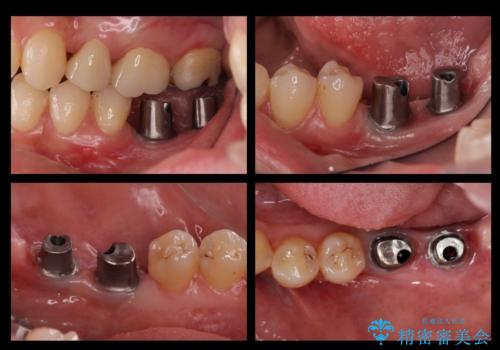

- 奥歯が二本欠損しており、その奥に親知らずが残っていました。

インプラントの一時手術と親知らずの抜歯を同時にしています。

- 70.2万円費用は治療当時の料金となります